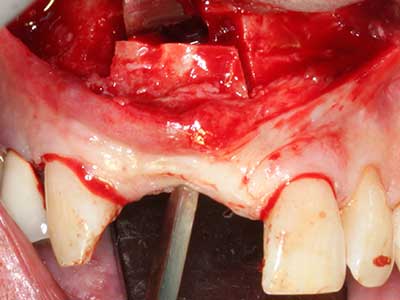

Abb. 2: Vertikaler und horizontaler seitlicher Oberkieferdefekt bei hoher Lachlinie mit Indikation zur präimplantologischen Rekonstruktion.

Abb. 3: Die basale Abtrennung des Blocks wird durch speziell abgewinkelte Aufsätze erleichtert.

Abb. 4: Mit dem Knochenschaber werden zusätzliche Eigenknochenspäne gewonnen.

Abb. 5: Überprüfung der Blockdimension am Empfängergebiet.